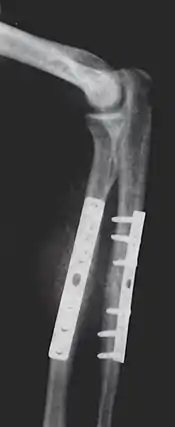

Advances made in surgical technique during the 18th century, such as John Hunter's research on tendon healing and Percival Pott's work on spinal deformity steadily increased the range of new methods available for effective treatment. Robert Chessher, a pioneering British orthopedist, invented the double-inclined plane, used to treat lower-body bone fractures, in 1790.[6] Antonius Mathijsen, a Dutch military surgeon, invented the plaster of Paris cast in 1851. Until the 1890s, though, orthopedics was still a study limited to the correction of deformity in children. One of the first surgical procedures developed was percutaneous tenotomy. This involved cutting a tendon, originally the Achilles tendon, to help treat deformities alongside bracing and exercises. In the late 1800s and first decades of the 1900s, significant controversy arose about whether orthopedics should include surgical procedures at all.

The use of intramedullary rods to treat fractures of the femur and tibia was pioneered by Gerhard Küntscher of Germany. This made a noticeable difference to the speed of recovery of injured German soldiers during World War II and led to more widespread adoption of intramedullary fixation of fractures in the rest of the world. Traction was the standard method of treating thigh bone fractures until the late 1970s, though, when the Harborview Medical Center group in Seattle popularized intramedullary fixation without opening up the fracture.

- Repair fracture of radius (bone)/ulna